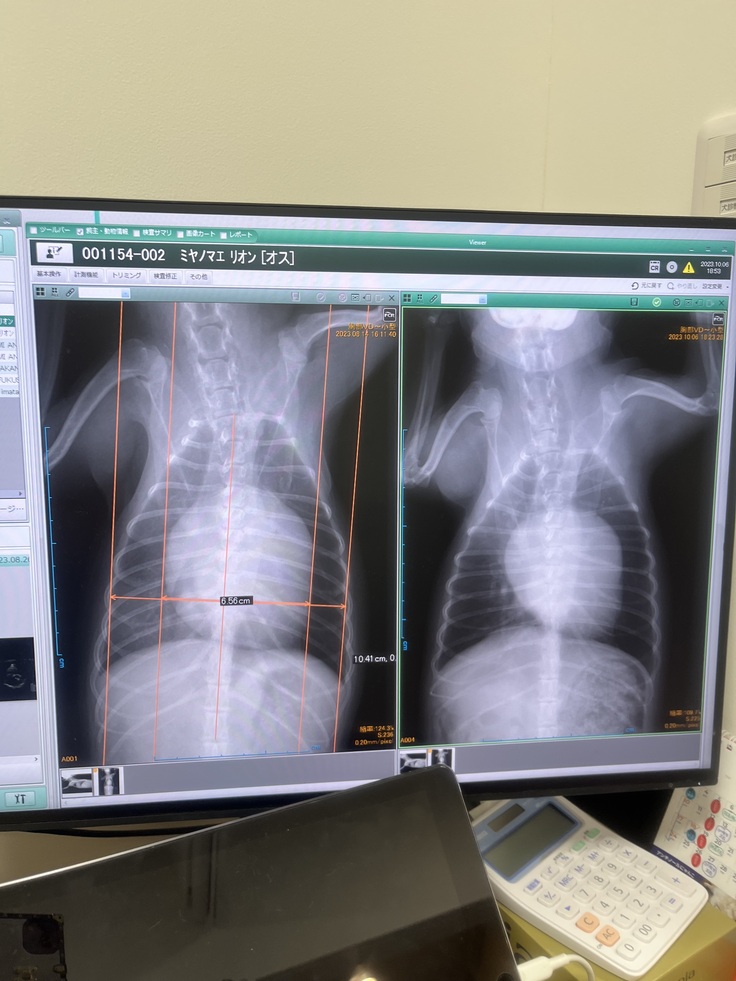

左が8/14 右が10/6

少し心臓が小さくなりました😌✨